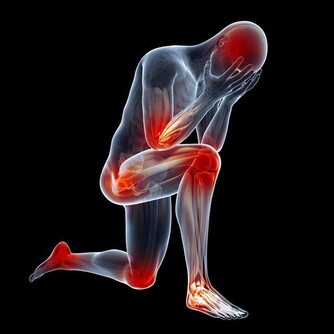

五、遠離菸酒